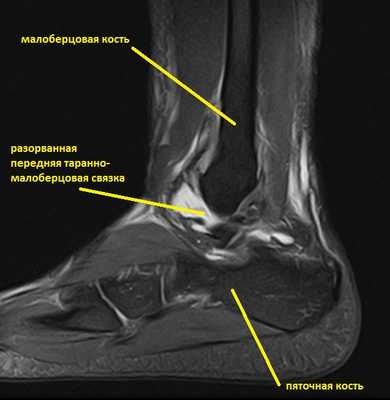

Ниже представлены срезы МРТ в которых наглядно показано расположение повреждённых связочных структур.

Данные повреждения практически в 100 % случаев пропускаются при первичном обращении в травмпункт. При несвоевременном или неадекватном лечении нестабильность голеностопного сустава приводит к разрушению суставного хряща, выраженной боли, деформации, и в конечном счёте к полной утрате функции опоры и ходьбы. В зависимости от того какие связки разорваны и от того насколько выражена нестабильность, артроз развивается в разные сроки, от 1 года при разрыве синдесмоза, до 20 и более лет при изолированном разрыве передней таранно-малоберцовой связки.

На этом этапе пациентка лечилась по стандартному сценарию «растяжение голеностопа». Носила ортез, мазала голеностоп вольтареном и лиотоном, разгружала его при помощи трости. Но в связи с длительно сохраняющимся болевым синдромом было выполнено МРТ, при котором диагностирован застарелый разрыв передней таранно-малоберцовой связки, пяточно-малоберцовой связки правого голеностопного сустава, контузионное повреждение латеральных отделов таранной кости.